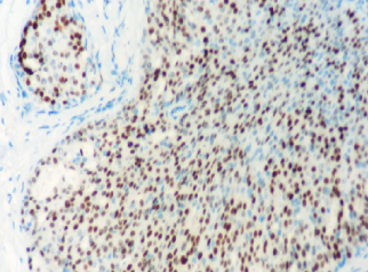

免疫组化

ER弥漫强+,Her2-,ki67低表达

具有神经内分泌表达:CgA、Syn(约70%的比例,阳性细胞表达不等)

CK5/6、CKH-,可斑驳性的残留

肌上皮内-,导管周可-可+